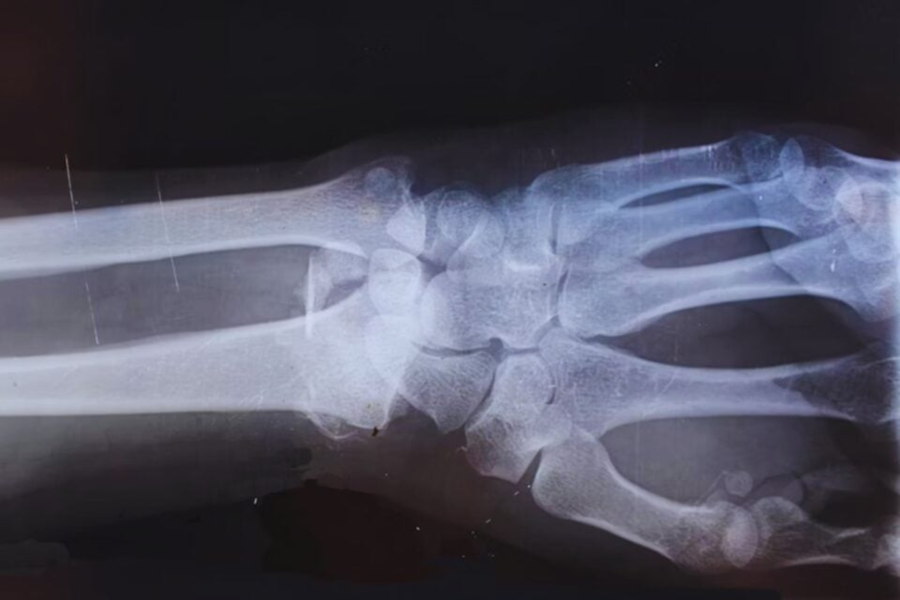

O uso da cola chinesa pode representar um avanço significativo para a ortopedia moderna. Atualmente, fraturas graves muitas vezes exigem procedimentos cirúrgicos invasivos, com implantação de materiais metálicos e posterior retirada em alguns casos. Esse processo pode gerar riscos adicionais, como infecções e complicações durante a recuperação.

Com a Bone 02, seria possível reduzir o tempo de internação e eliminar a necessidade de uma segunda cirurgia para retirada de implantes. Isso impactaria diretamente os custos hospitalares e o bem-estar do paciente. Além disso, o fato de o produto ser biodegradável garante que o corpo não precise lidar com resíduos permanentes após a cicatrização.